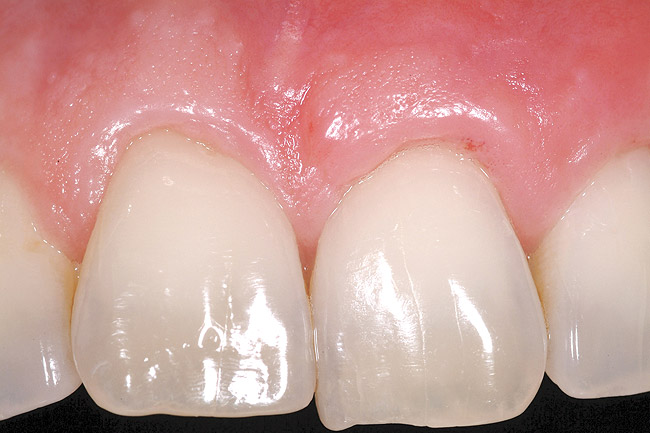

Figure 1  Case One Pretreatment clinical view, Case 1, maxillary right.

Figure 1

A 54-year-old non-smoking woman presented for correction of deep-wide gingival recession in the maxillary anterior (Figure 1 through Figure 3). The patient’s desires were to correct the gingival recession, balance the heights of contour of the tissues, and possibly undergo esthetic enhancement of the maxillary anterior with veneer restorations.

A 27-year-old non-smoking man presented for esthetic enhancement of the left central incisor, which had a pre-existing full-coverage restoration that required replacement (Figure 16). The patient had begun orthodontic treatment in the mandibular arch to correct a minor occlusal imbalance and required coronal repositioning and soft tissue grafting to correct gingival recession at the facial of the right canine, in addition to correction of the free gingival margin at the facial of the left central incisor, which was asymmetrical to the free gingival margin of tooth No. 8. Additionally, the facial gingival tissues were of a thin biotype, which at the facial surface of the left central incisor allowed for the darkened root surface to be visible through the tissue (Figure 16).